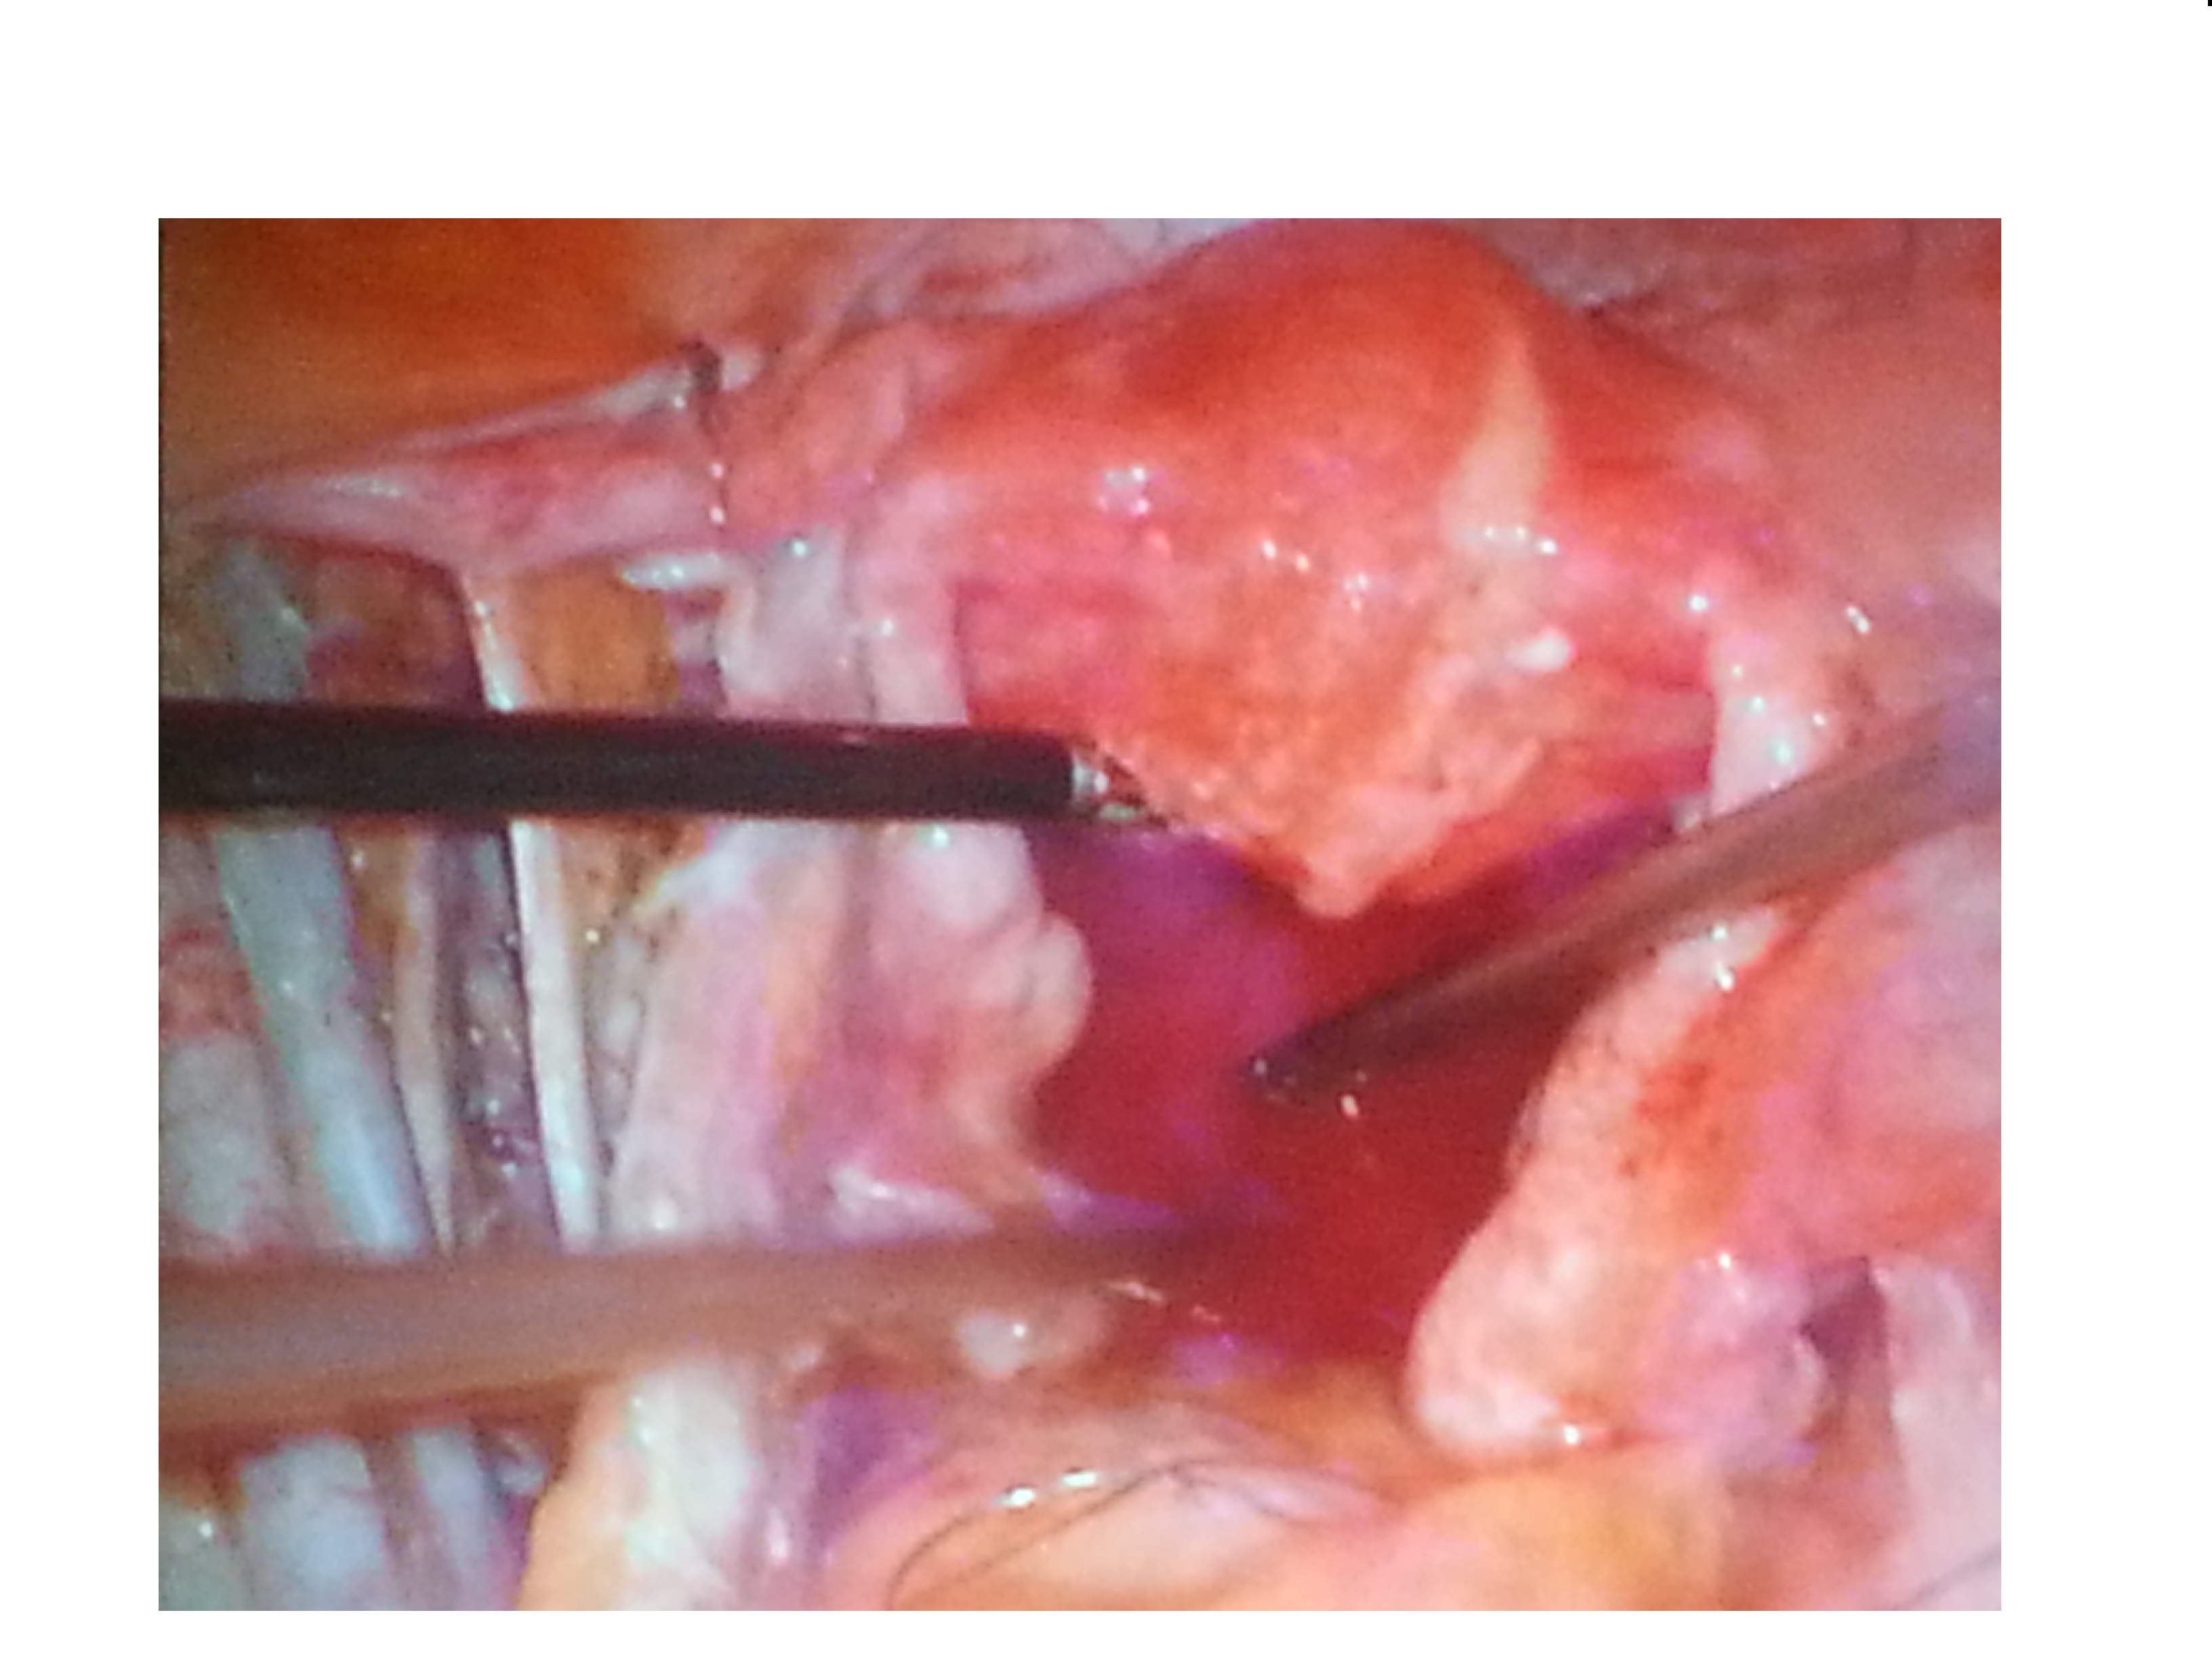

妇科开展:腹腔镜子宫肌瘤剔除术、子宫切除术、卵巢肿瘤切除术、宫颈癌根治术、卵巢癌减灭术,输卵管微整形术,宫腔镜检查及电切术,并开展钬激光治疗(全国领先),无脱垂大子宫肌瘤患者的阴式子宫切除术(省内领先)等先进技术。